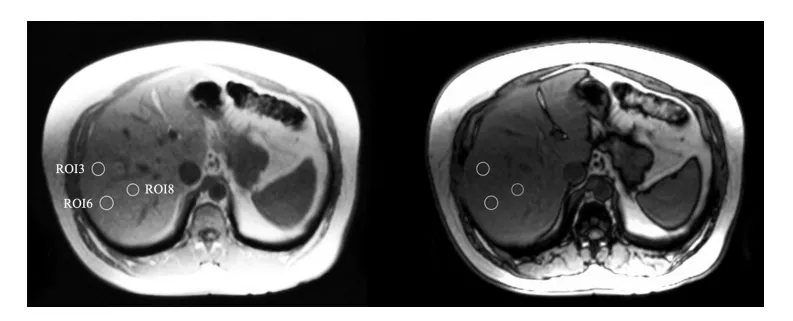

| 主要評価項目 | MRIによる肝脂肪含量の変化 |

主な評価項目は、MRI(磁気共鳴画像法)で測定した肝臓内の脂肪含量である。副次的な評価項目として、血液中の肝酵素、脂質プロファイル、ホルモン値、体組成を測定した。

MRIを用いて肝臓内の脂肪含量を測定し、水素水群とプラセボ群の変化を比較した。

水素水群では肝臓全体で脂肪が有意に減少し、プラセボ群では同様の変化は見られなかった。減少の度合いは部位によって異なり、肝臓全体では約3%、表面付近(被膜付近)では約25%の減少が観察された(p < 0.05)。